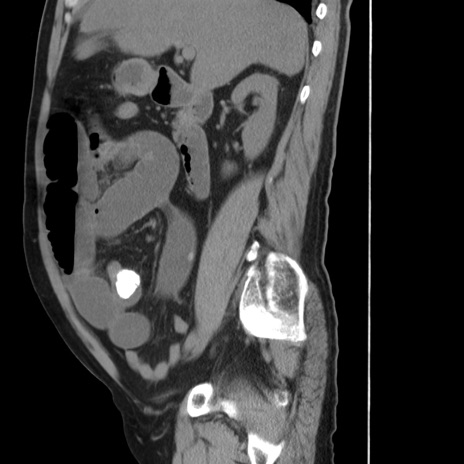

症例20(矢状断像)

【症例】 60歳代男性

【主訴】 腹部膨満、嘔吐

【現病歴】5日前頃より倦怠感を認め食事量減少し4日前の朝嘔吐、食事摂取困難となった。 3日前近医受診し点滴施行され整腸剤などを処方された。 当日他院を受診し、腹部膨満著明、炎症反応の上昇(CRP10.8、WBC11200)あり、紹介受診となる。

【身体所見】 意識JCS1 受け答えがはっきりしないBP 111/57mHg、 P 67bpm、、BT35.2°C、SpO2 97%(RA)、 腹部:膨隆、打診で鼓音あり、全体的に圧痛有り、腸蠕動音(-)、反跳痛ははっきりせず。

【データ】WBC 11400、CRP 14.20